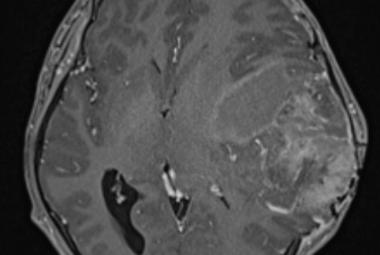

Homonymous Hemianopia Associated with COVID-19 Vaccination